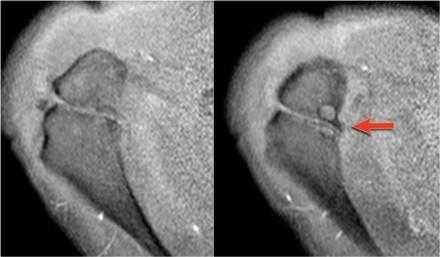

Вид в положении отведения и поворота плеча кнаружи (ABER)

Повреждения суставной губы

Изображения в положении отведения и поворота плеча кнаружи является наилучшим для оценки передненижних отделов суставной губы в положении 3-6 часов, где локализуется большинство ее повреждений. В положении отведения и поворота плеча кнаружи суставно-плечевая связка растягивается напрягая передне-нижние отделы суставной губы, позволяя внутрисутавному контрасту попасть между повреждением губы и суставной впадиной.

Изображения в положении отведения и поворота плеча кнаружи получаются в аксиальной плоскости путем отклонения на 45 градусов от коротальной плоскости (см. иллюстрацию).

В этом положении область на 3-6 часов ориентирована перпендикулярно.

Обратите внимание на красную стрелку указывающую на небольшое повреждение Пертеса, которо не визуализировалось при стандартной аксиальной ориентации.